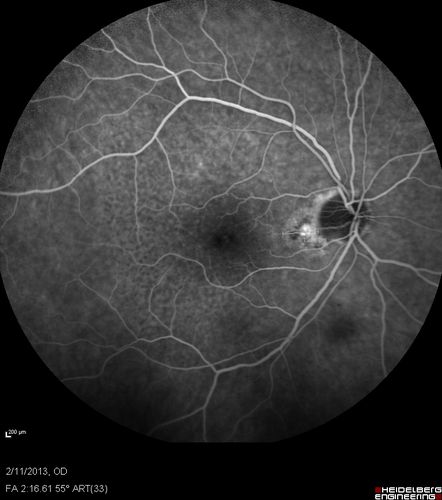

Asymptomatic Juxtapapillary Choroidal Neovascular Membrane - Reticular Macular Disease (Wet AMD)

Asymptomatic Juxtapapillary Bilateral Wet AMD - Reticular Macular Disease - Heidelberg Color Photos